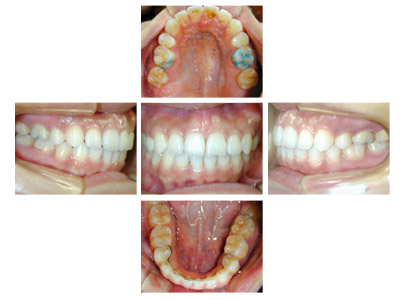

![]() |

犬歯関係・臼歯関係は良好ですので、かみ合わせを崩さないように矯正治療をすすめます。

上下顎前歯の叢生を改善するために上下顎両側第1小臼歯を4歯抜歯して治療します。

0.14インチラウンドのニッケルチタンワイヤーで治療開始して0.16×0.16レクタンワイヤーで治療をすすめていき叢生を改善します。

できたスペースを利用して叢生の改善と臼歯のかみ合わせの改善を行います。

治療開始前には抜歯について強い拒否があるように見えました。

治療開始初期には体調の不良が断続的にありましたが、治療がすすむにつれてキャンセルがなくなり比較的順調に治療がすすみました。

治療の前に叢生のためずれていた中切歯の正中は一致しています。犬歯関係、臼歯関係も1対2歯でよく咬んでいます。

口腔衛生状態が治療中に不良でした。

装置がとれ、歯列が改善されたので口腔衛生状態の改善を期待してブラッシング等のオーラルセルフケアに重要性を説明しました。

後戻りを防ぐには保定が重要でリテーナーの使用を強く指導しました。

治療費用:60万円

動的治療期間:2年4か月